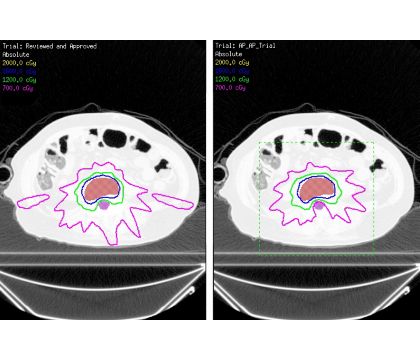

Generate high quality plans on the first pass

The Auto-Planning engine optimizes target coverage and OAR sparing. It reduces the need for multiple plan reviews with the physician and physicist, and runs in the background leaving time free for other tasks.